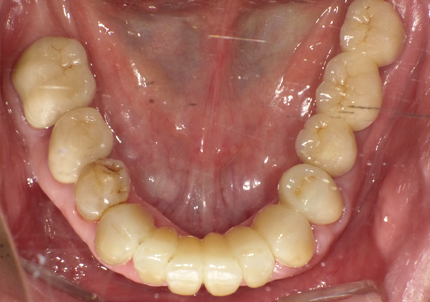

10.口腔内写真(2022年2月)

特に問題無く経過はとても良いです。

患者様ご本人も「良く咬めてとても良い」と満足されています。

11.口腔内写真(2025年6月)

右下2本初診より9年経過、左下3本埋入後4年経過、ともに経過良好。